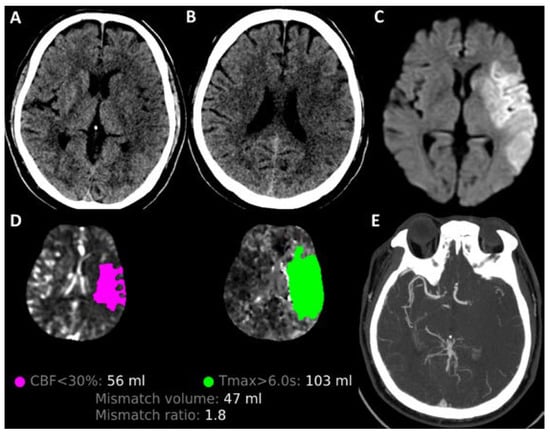

2. Imaging Considerations in Large Infarct Core Strokes